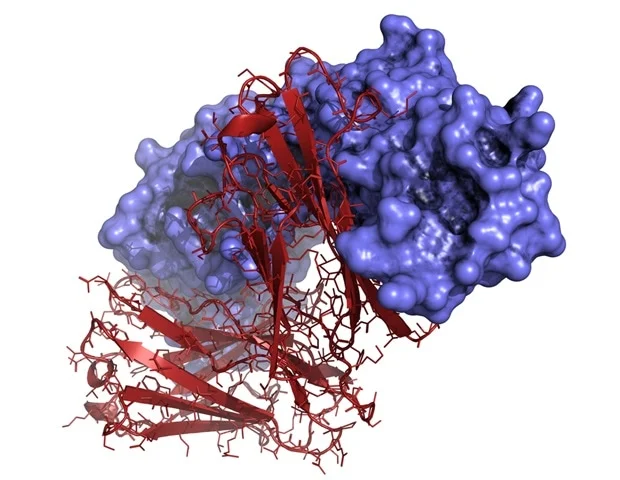

מהנדסים מאוניברסיטת פנסילבניה פיתחו סוג חדש של ננו-חלקיקי שומנים (LNP) שיוכל לשמש יום אחד כאימונותרפיה אוניברסלית לסרטן היוצרים גידולים מוצקים,

מהנדסים מאוניברסיטת פנסילבניה פיתחו סוג חדש של ננו-חלקיקי שומנים (LNP) שיוכל לשמש יום אחד כאימונותרפיה אוניברסלית לסרטן היוצרים גידולים מוצקים,